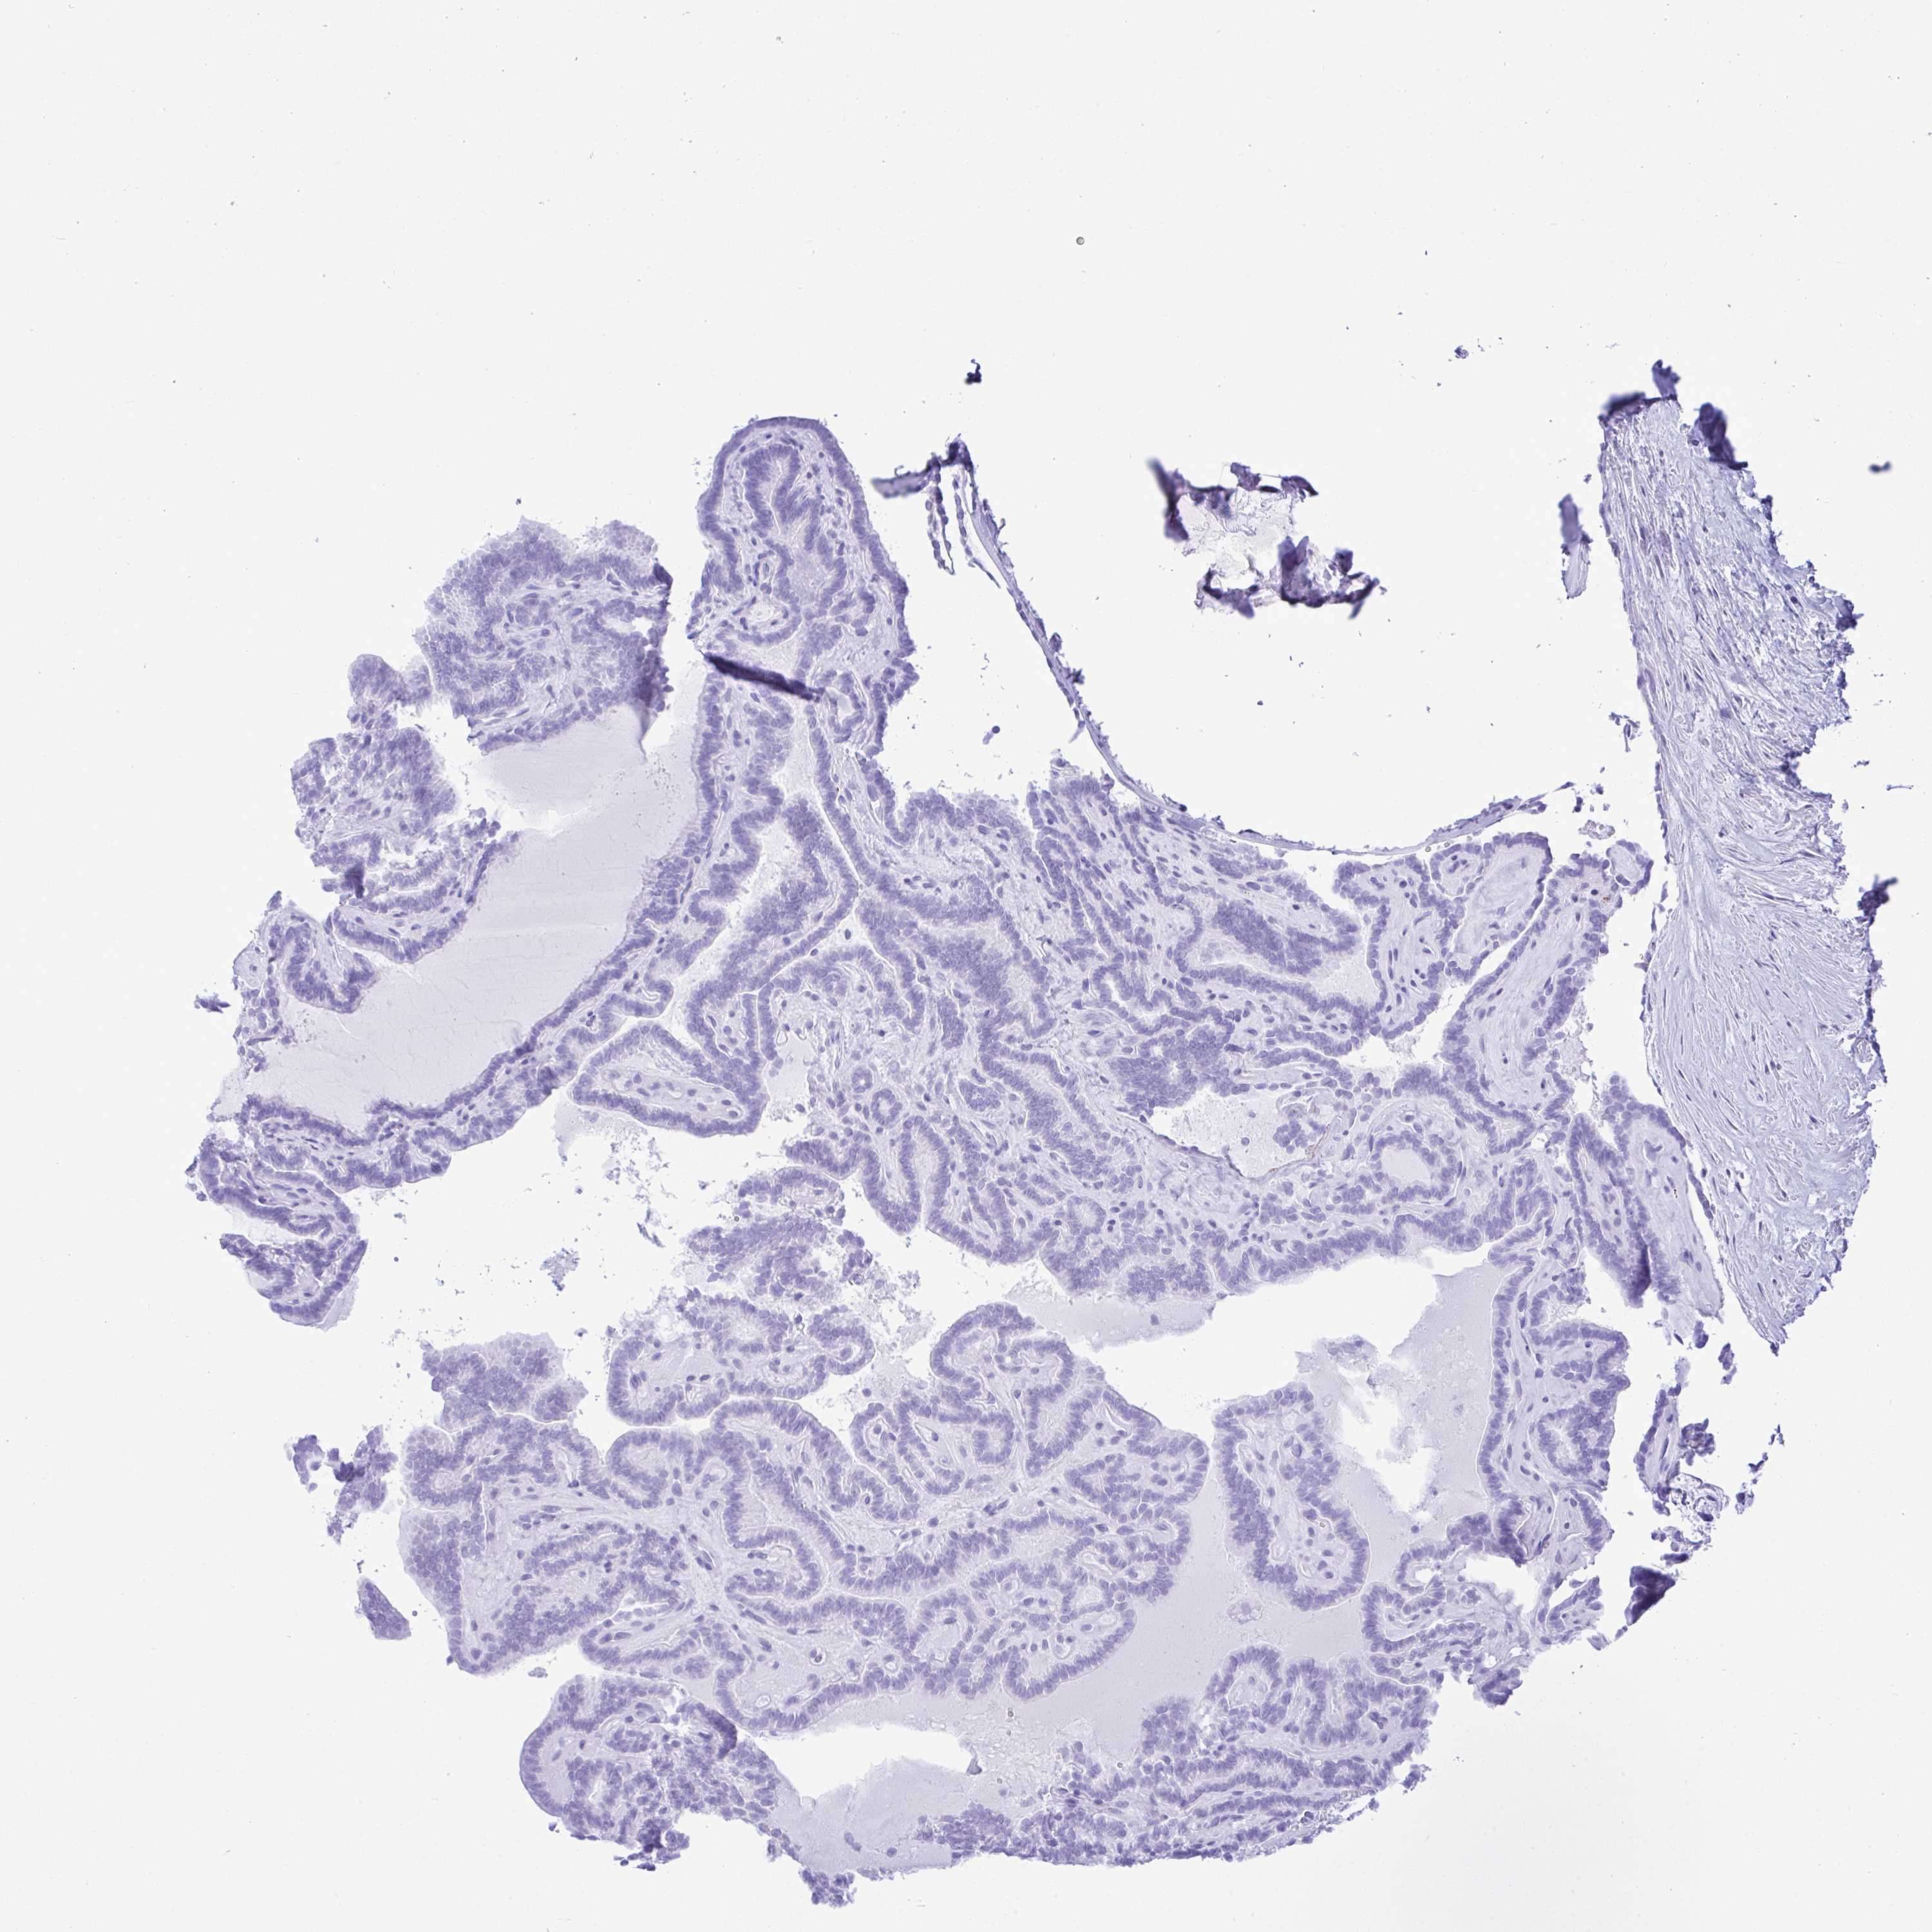

THYROID CANCER - Protein expressioni

A mouse-over function shows sample information and annotation data. Click on an image to view it in a full screen mode. Samples can be filtered based on level of antibody staining by selecting one or several of the following categories: high, medium, low and not detected. The assay and annotation is described here.

Note that samples used for immunohistochemistry by the Human Protein Atlas do not correspond to samples in the TCGA dataset.

Antibody stainingi

Antibody staining in the annotated cell types in the current human tissue is reported as not detected, low, medium, or high, based on conventional immunohistochemistry profiling in selected tissues. This score is based on the combination of the staining intensity and fraction of stained cells.

Each image is clickable and will lead to virtual microscopy that enables deeper exploration of all samples and also displays staining intensity scores, fraction scores and subcellular localization as well as patient and tissue information for each sample.

Antibody HPA059274

Staining

High

Medium

Low

Not detected

Intensity

Strong

Moderate

Weak

Negative

Quantity

>75%

75%-25%

<25%

None

Location

Nuclear

Cytoplasmic/membranous

Cytoplasmic/membranous,nuclear

Papillary adenocarcinoma, NOS

Follicular adenoma carcinoma, NOS